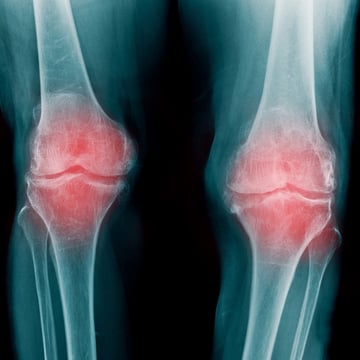

【変形性膝関節症(膝OA)高齢膝】 変形性膝関節症でお悩みの方はいませんか? 変形性膝関節症とは、特に女性に多く見られる症状で年齢が上がるほど罹患率は高くなります。 近年の生活習慣の影響で40代から膝の内側に痛みを抱える方も増えてきています。 放置してしまうと骨に負担がかかり変形性膝関節症の症状が出現してしまいます。...